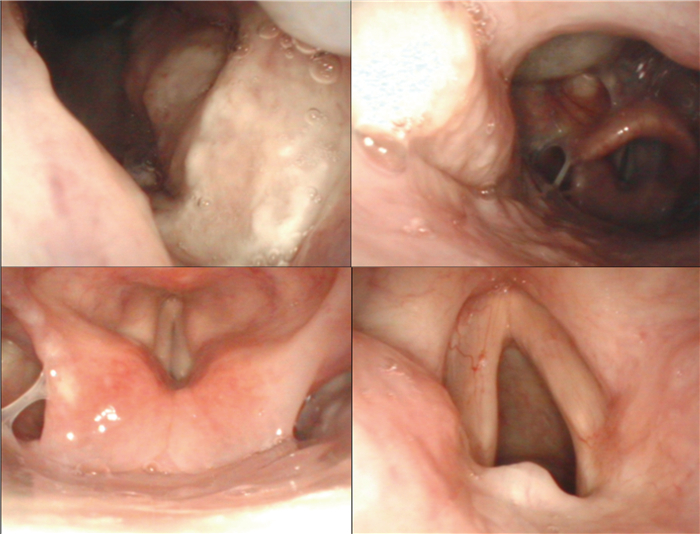

1.2 检查结果进一步完善检查,结果如下。β-D-葡聚糖(β-D-glucan, G)试验:127 pg/mL,半乳甘露聚糖(galactomannan, GM)抗原试验:1.67 s/co;头颅、鼻咽部及颈部磁共振成像(magnetic resonance imaging,MRI)提示:延髓左侧异常信号,不排除转移性病变,前颈部多发淋巴结,部分肿大、融合(见图 2)。喉镜提示:双侧圆枕见新生物,其表面覆盖白色伪膜样物,左侧咽侧壁、舌根部隆起,左侧声带后上方见囊肿样物,双侧梨状窝光滑,左侧声带固定,右侧声带运动正常(见图 3)。2次颈部及腋窝淋巴结穿刺涂片见细胞内外大量圆形、卵圆形直径约2~4 μm的孢子,多呈两头钝圆、中间有横膈的腊肠形,考虑为马尔尼菲篮状菌病(见图 4)。与此同时血培养瓶内涂片镜检下见丝状真菌生长。随后,将淋巴结穿刺物分别在25 ℃和37 ℃沙保罗培养基中培养1周,观察到在25 ℃培养条件下,菌落呈黄绿色,并见红色可溶性色素深入培养基中,显微镜下见典型的扫帚状有隔菌丝及端生分生孢子;在37 ℃培养时,菌落为白色、褐色奶油状,无色素产生,显微镜下呈带横隔的腊肠形孢子(见图 5)。

A, C: Increased lymph nodes in the anterior neck, partial enlargement and fusion in MRI examination. B, D: Abnormal signal on the left side of medulla oblongata in MRI examination. 图 2 头颅、鼻咽部及颈部MRI检查结果(2021年4月) Fig. 2 MRI examination results of the head, nasopharynx and neck (April 2021) |

本例报道中,患者起初仅表现为“咽痛”,经鼻咽镜及喉镜检查发现鼻咽部溃疡、圆枕新生物(覆伪膜样物)、声带后上方囊肿样物,均为马尔尼菲篮状菌感染上呼吸道表现,后在病程发展中逐渐出现发热、咳嗽、白痰、氧饱和度下降等下呼吸道症状;腹痛、解柏油样便,以及腹部影像学见腹腔积液,均为消化道表现;此外见典型皮肤囊性丘疹及脐凹样疹,以及颈部及腋窝浅表淋巴结肿大,影像检查见纵隔、腹膜后及肠系膜走行区淋巴结增多、肿大,较大者直径达2.0 cm。本例患者住院期间出现左侧眼睑上抬困难,伴有左侧眼球活动受限、轻度吐词不清、口角歪斜,头颈部MRI提示延髓左侧异常信号,考虑为马尔尼菲篮状菌病中枢神经系统受累的表现,较为少见,抗真菌治疗后随访上述症状均好转,复查MRI提示病灶明显缩小,进一步印证该患者为中枢神经系统受累。

本例患者CT检查见颈部、纵隔、腹膜后及肠系膜淋巴结肿大,双侧肾上腺明显增粗,腹腔积液,均考虑为马尔尼菲篮状菌感染表现,另外延髓左侧出现的异常信号,喉镜下双侧圆枕覆盖白色伪膜样新生物,左侧咽侧壁、舌根部隆起,左侧声带后上方见囊肿样物,考虑为该病原累及中枢神经系统及上呼吸道的表现。患者经抗真菌治疗后,咽痛好转,痰液分泌减少,左侧眼睑不能睁开、左侧眼球活动受限、轻度吐词不清、口角歪斜等情况逐渐好转,经影像学复查肿大的淋巴结消失,肾上腺正常,延髓病变明显缩小。